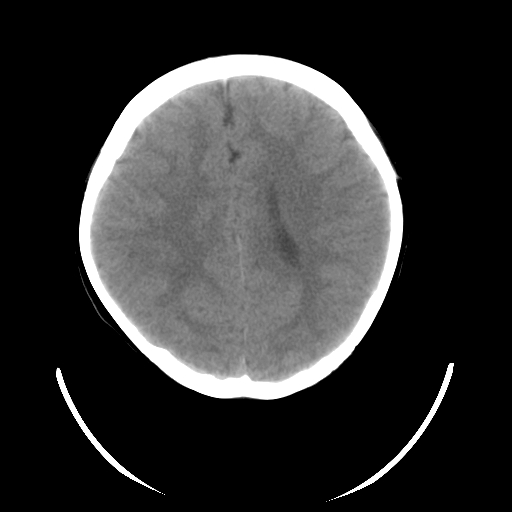

女,6岁,头痛、呕吐一天。

颅脑ct平扫未见明显异常。

头颅ct平扫未见明确异常,随诊复查。